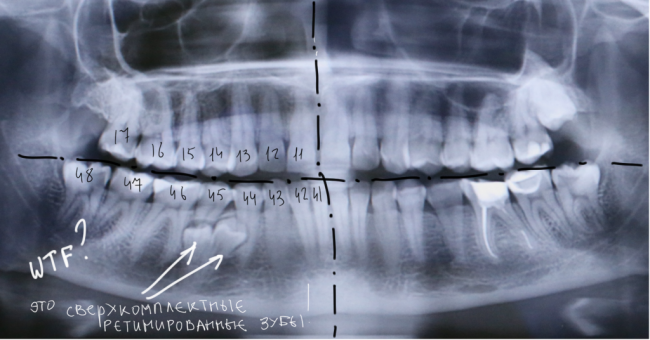

Современная медицинская наука — все ли средства хороши?